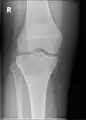

A variety of imaging studies can be used to diagnose chondroblastoma, with radiographs being the most common.[10][8] Laboratory studies are not considered useful.[14] Classical chondroblastoma (appearing on long bones) appears as a well-defined eccentric oval or round lytic lesion that usually involves the adjacent bone cortex without periosteal reaction.[10][13] A sclerotic margin can be seen in some cases.[10][13] For long bone chondroblastomas the tumor is typically contained to the epiphysis or apophysis but may extend through the epiphyseal plate.[10][13] Chondroblastomas are usually located in the medullary portion of bones and can, in some cases, include the metaphysis.[10][13] However, true metaphyseal chondroblastomas are rare and are typically the result of an extension from a neighboring epiphyseal legion.[10][13] Most lesions are less than 4 cm.[10] A mottled appearance on the radiograph is not atypical and indicates areas of calcification which is commonly associated with skeletally immature patients.[10] Additionally, one-third of all cases involve aneurysmal bone cysts which are thought to be the result of stress, trauma or hemorrhage.[10] In cases involving older patients or flat bones, typical radiographic presentation is not as common and may mimic aggressive processes.[10][13]

1. a. X-ray of chondroblastoma of thigh bone near knee

3. X-ray of chondroblastoma of large long bone of lower leg, near the knee